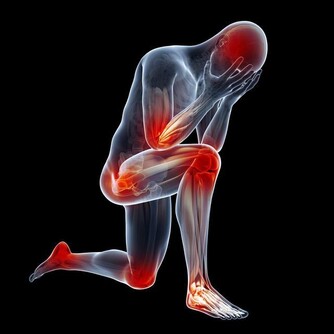

(各穴位所在圖)

2. 膕窩穴位:委中穴

常按摩此處,對治坐骨神經痛有效果

提醒:膕窩囊腫患者不適合按摩該部位

膕窩是膝後區的菱形凹槽,裡面的血管和神經非常豐富,

經常拍打有行氣活血、緩解痙攣的功效。

膕窩處一個很重要的穴位叫委中穴,經常按摩,

對常見的坐骨神經痛、小腿疲勞、脖子痠痛、臀部疼痛等疼痛性疾病有良好作用。

南京市中西醫結合醫院骨科副主任醫師王睿說,

委中穴在膕窩正中,為人體足太陽膀胱經上的重要穴道之一,

主治疾病為:坐骨神經痛、小腿疲勞、肚子疼痛等。

但有一種情況是不適合按摩和刺激這個部位的。

那就是膕窩囊腫的患者,膕窩囊腫泛指膕窩內的滑囊炎,

是因為膝關節積液,屈膝時腔內壓力增高,迫使滑液後移形成的一種疾病,

如果給予按摩刺激,不但不利於健康還會延誤治療。